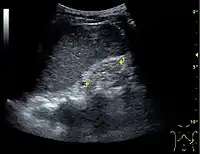

Figure 10. Solid tumor in the renal sinus seen as a hypoechoic mass, later found to be lymphoma. The '1' and '2' on the US image are reference points used for CT fusion (not shown).[1]